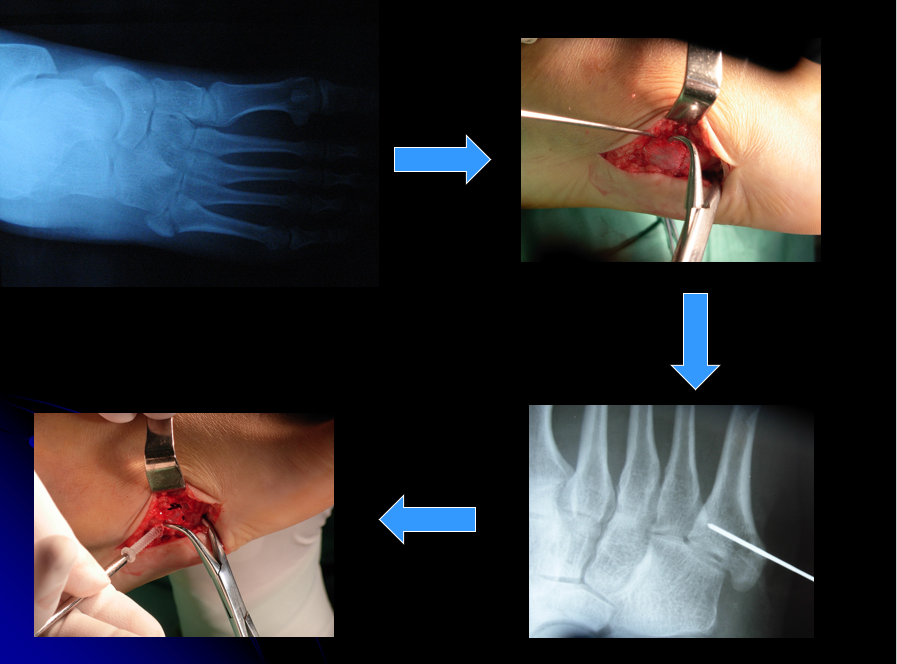

克氏针固定传统的固定方式,单纯克氏针固定操作简单,但无断端加压且固定不牢靠。

经皮空心钉固定适合于骨折块较大,移位较少,骨质好的患者。具有微创损伤小、不干扰局部的血运、固定牢靠、恢复快等优点。

操作要点:操作要在透视监视下进行,且导针一定要从尖端打入,且在第四、五跖骨间连接以远穿出对侧骨皮质,这样生物力学强度最佳。

微型锁定钢板螺钉固定固定坚强,术后可以佩戴前足减压支具早期活动 ,适用于骨块较大,要求较高的患者。弊端是费用较高,需二次取出。

操作要点:板钉直径以2.0 mm为宜,远近端至少保证2枚螺钉。

骑缝钉固定固定强度可靠,且操作方便,有效避免了螺钉操作时骨折块爆裂的风险,其弊端有:

• 没有骨块间加压作用,适合小骨块;

• 不锈钢材质需二期取出。

操作要点:先以克氏针临时固定后再行骑缝钉固定,根据情况采用1-2枚,避免针穿入关节面。